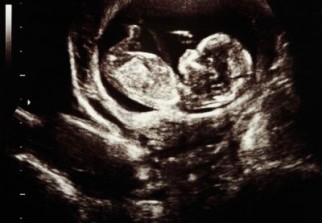

Un test de l'ADN du foetus circulant dans le sang de la mère serait plus efficace que les tests standards pour détecter la trisomie 21 ainsi que deux autres anomalies chromosomiques moins fréquentes, indique une étude publiée mercredi.

Les analyses ont été effectuées grâce à la faible quantité d'ADN foetal se trouvant dans le sang maternel, selon les résultats de cette étude parue dans une revue médicale américaine qui a porté sur 16.000 femmes dont la grossesse allait de dix à quatorze semaines.

Elles ont permis d'identifier la trisomie 21 chez tous les 38 foetus affectés. Les résultats ont été confirmés par des examens du nouveau-né ou prénataux, ainsi que par des analyses génétiques post-natales.

Une quantité plus importante d'ADN du foetus circulant dans le sang de la mère est en effet une possible indication de certaines anomalies chromosomiques,dont la trisomie qui se caractérise par une copie supplémentaire d'un chromosome formant une des 23 paires de chromosomes.

Les techniques standard de dépistage appliquées au même groupe de femmes a détecté la trisomie chez 30 des 38 foetus, ont précisé les chercheurs.

Les femmes examinées pour l'étude étaient âgées de 30 ans en moyenne et environ 25% avaient plus de 35 ans, un âge à partir duquel on estime que le risque de trisomie 21 augmente fortement.